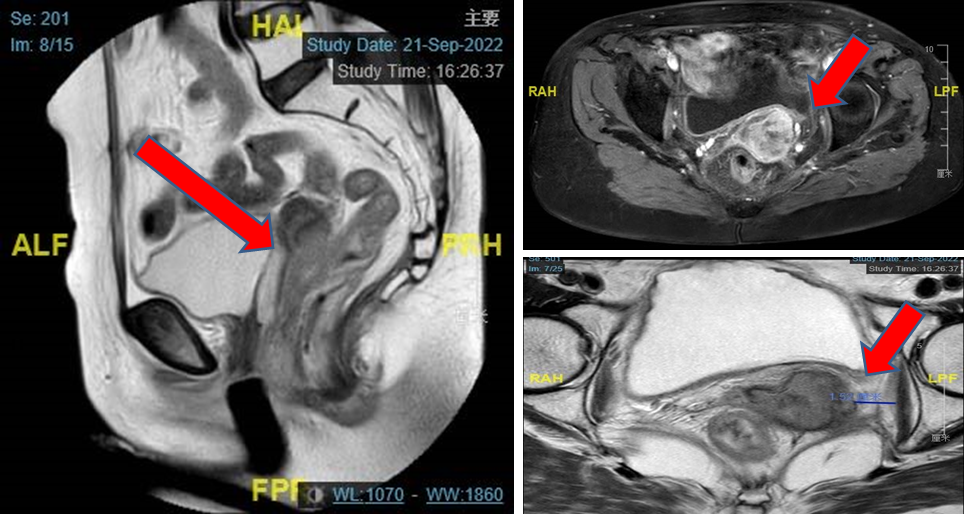

PET-CT检查:阴道全程壁增厚,FDG代谢增高,病灶累及宫颈,与直肠及膀胱前壁分界不清,考虑肿瘤复发可能大,病灶侵犯直肠及膀胱可能。

图4. PET-CT提示阴道后壁肿瘤复发,SUV值高,病灶与直肠及膀胱前壁分界不清,考虑病灶侵犯直肠及膀胱可能,另有可疑转移灶

MRI检查:阴道后壁肿瘤变大,且与肛提肌分界欠清,考虑为引起下腹疼痛的原因。

图5. MRI提示阴道后壁肿瘤变大,且与肛提肌分界欠清